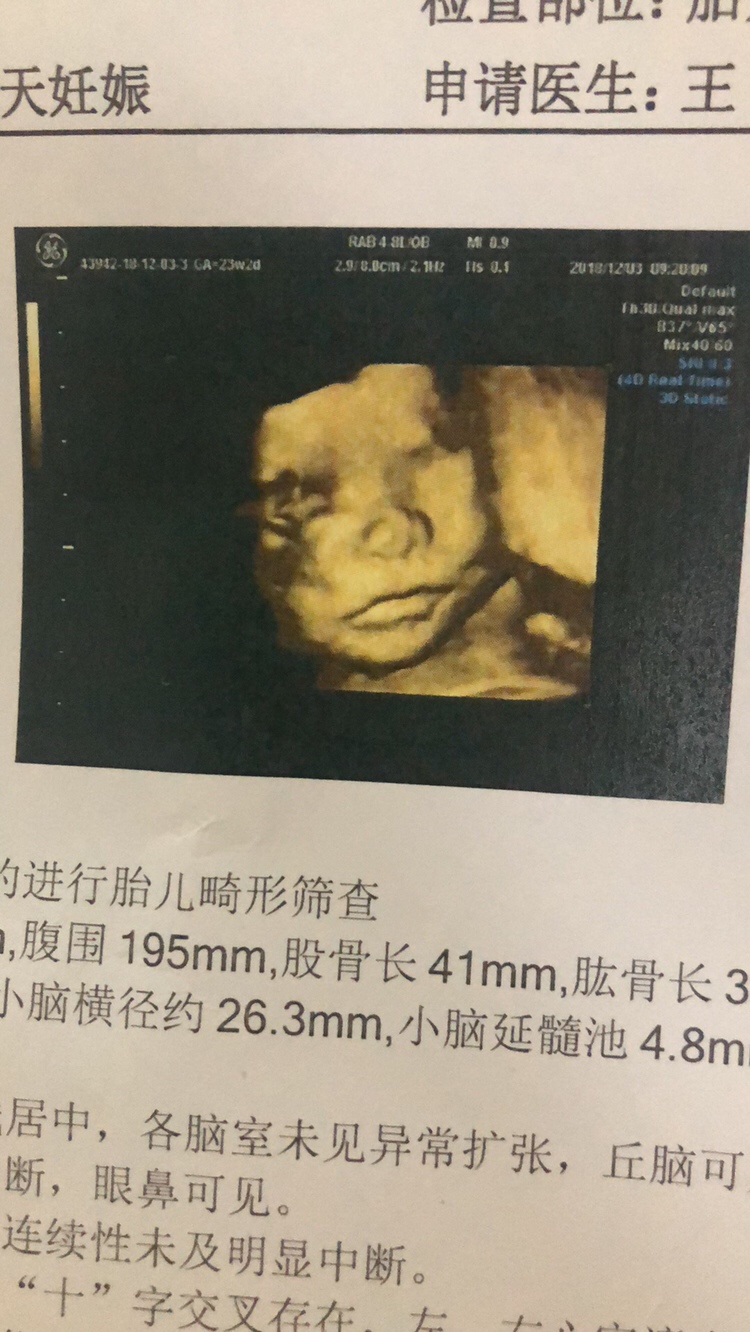

孕24周+5天

四维的照片都好丑啊

这鼻子也挺大的呀😂😂